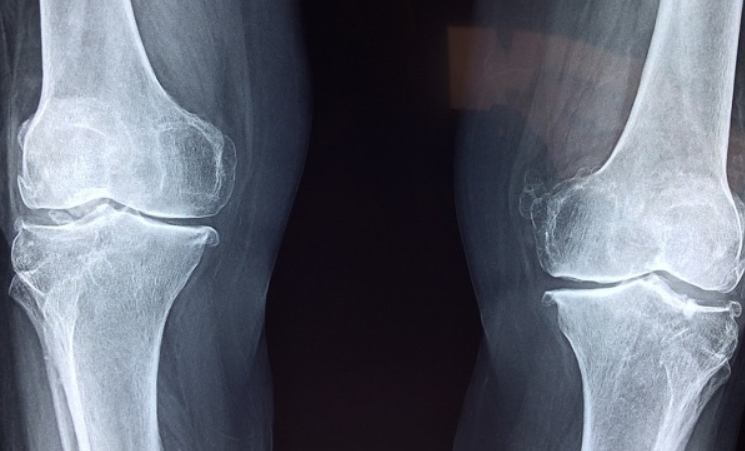

무릎 관절염 초기증상

무릎 관절염의 초기증상은 무릎 통증과 함께 관절의 뻣뻣함으로 시작됩니다. 특히, 아침에 일어났을 때나 장시간 앉아 있다가 일어날 때 통증이 심해질 수 있습니다. 계단을 오르내릴 때 무릎에 심한 통증을 느낄 수 있으며, 무릎이 붓고 열감이 있을 수 있습니다. 무릎을 구부리거나 펼 때 걸리는 느낌이 들거나, 움직임이 제한될 수 있습니다.

퇴행성 관절염 초기증상

퇴행성 관절염은 관절의 연골이 닳아 없어지면서 발생하는 질환입니다. 초기에는 관절의 통증과 경직이 주요 증상으로 나타납니다. 아침에 일어나면 관절이 뻣뻣해지고, 활동을 시작하면 증상이 완화되는 경향이 있습니다.

관절을 많이 사용할수록 통증이 심해지며, 밤에는 통증이 더 심해질 수 있습니다. 관절이 붓고 움직임이 제한될 수 있으며, 관절 주변 근육이 약해질 수 있습니다.